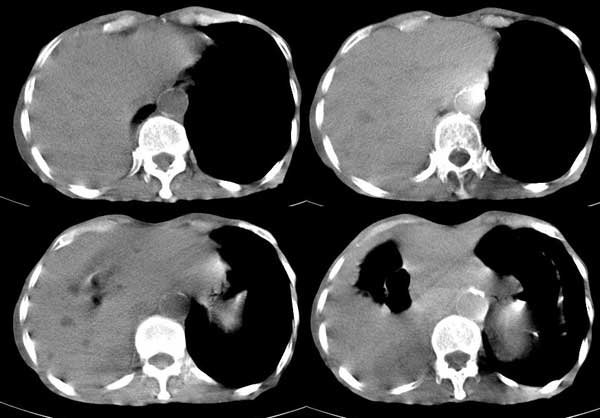

患者男,81岁,咳喘10余年,继往结核病史,发现胸部体表肿物(具体时间不详)就诊

右侧胸廓塌陷。右前上外侧胸壁软组织肿块,其内见有低密度影,肋骨呈溶骨性表现。右肺上叶见大量的间质纤维化表现。右侧膈肌上抬。

患者男,81岁,咳喘10余年,继往结核病史,发现胸部体表肿物

考虑:1、继发性结核,右结核性胸膜炎伴胸壁结核性感染

2、右侧胸壁恶性肿瘤。

患者男,81岁,咳喘10余年,继往结核病史,发现胸部体表肿物。

考虑:1 右侧胸壁恶性肿瘤(多考虑:胸膜间皮瘤)。

2 继发性结核,右结核性胸膜炎伴胸壁结核性感染。

右胸壁恶性肿瘤,以肉瘤可能性大